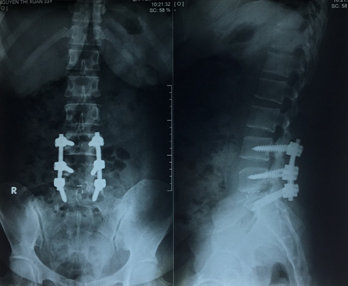

Hình 3. MRI thoát vị đĩa đệm di trú trên tầng L5/S1, chèn ép bao màng cứng và rễ thần kinh tương ứng. Lồi đĩa đệm ra sau L4/L5.

Khi khám thực thể, bệnh nhân đã tỉnh táo và định hướng và có dấu hiệu sinh tồn ổn định. Thử nghiệm Lasegue dương tính 30 độ cả hai chân, cơ lực tốt trong tất cả các nhóm cơ của chi dưới bên phải. Sức cơ của chi dưới bên trái đã giảm xuống còn 3 trên 5 trong các cơ hamstrings, và cơ tứ đầu đùi; 2-3 trên 5 (theo ASIA) trong các cơ bắp chân và duỗi ngón cái dài, ngắn. Phản xạ gân xương cho thấy bình thường phản xạ gân xương bánh chè, giảm phản xạ gân Achilles hai bên. Khám cảm giác: dị cảm khu vực quanh hậu môn. Phản xạ cơ thắt hậu môn đã giảm. X quang cột sống thắt lưng cho thấy hẹp nhẹ của các khoảng gian đốt sống L4/L5, L5/S1. Cộng hưởng từ (MRI) của thắt lưng cột sống cho thấy thoát vị đĩa đệm di trú trên tầng L5/S1, chèn ép bao màng cứng và rễ thần kinh tương ứng. Lồi đĩa đệm ra sau L4/L5, chèn ép bao màng cứng và rễ thần kinh tương ứng (Hình 3). Bệnh nhân được chẩn đoán thoát vị đĩa đệm L4/L5, L5/ S1 gây hội chứng chùm đuôi ngựa và được phẫu thuật cấp cứu. Phẫu thuật mở bản sống L4/l5, L5/S1 giải áp rộng rãi kèm cố định cột sống bằng vít qua cuống (Hình 4). Hậu phẫu, không có biến chứng gì, thiếu hụt cảm giác và vận động cải thiện; bệnh nhân vẫn giảm trương lực cơ thắt hậu môn và chưa có cảm giác đi tiểu lại. Bệnh nhân được chuyển đến đơn vị phục hồi chức năng cho trị liệu tiếp tục và hướng dẫn bệnh nhân đặt thông tiêu ngắt quãng. Hai tháng sau phẫu thuật, bệnh nhân đã có thể đi lại bình thường, mặc dù dáng đi rộng và chậm. Cảm giác đi tiểu và đại tiện cải thiện đáng kể 3 tháng sau phẫu thuật.

Hình 4. Phẫu thuật mở rộng ống sống L4-L5-S1 giải áp và cố định cột sống bằng vit qua cuống lối sau